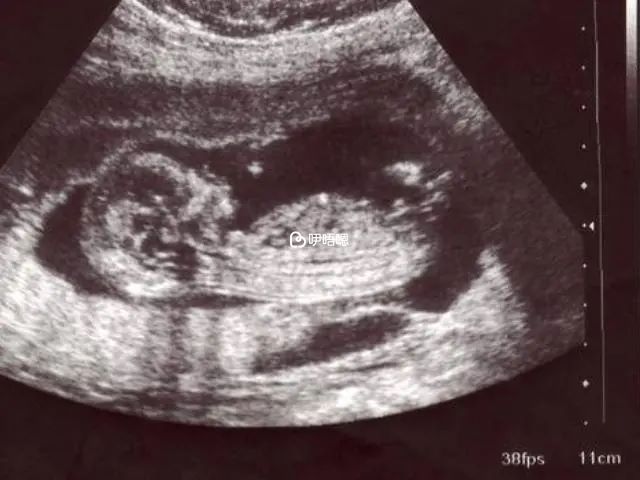

四維彩超是孕期最重要的檢查專案之一,是在妊娠22-26周之間做,在這個孕周範圍內,胎兒的各個臟器已經發育完善,並且大小比較適合排查胎兒畸形,所以孕婦應該選擇在這個時間段內做四維彩超。

四維彩超的最佳檢查時間是為懷孕的22-26周之間,孕婦處於這個時間段,寶寶的肢體以及主要臟器已經發育完全,並且羊水量也較適合做胎兒的排畸篩查,整個四維彩超的過程並不複雜,用不了多長時間就可全面瞭解寶寶的發育狀況,所以該項技術已經成為主流的檢測手段。

孕22-26周,胎兒的結構已經形成,寶寶的大小適中,並且在宮內的範圍較大,根據骨骼對於超聲回聲的影響較小,因此產生的影象也比較清晰,所以這個時間段做最好,但要注意的是,並非所有的孕周都適合做該項檢查,如果盲目做,那麼四維彩超對寶寶的影響就會很大,甚至危害胎兒健康發育。